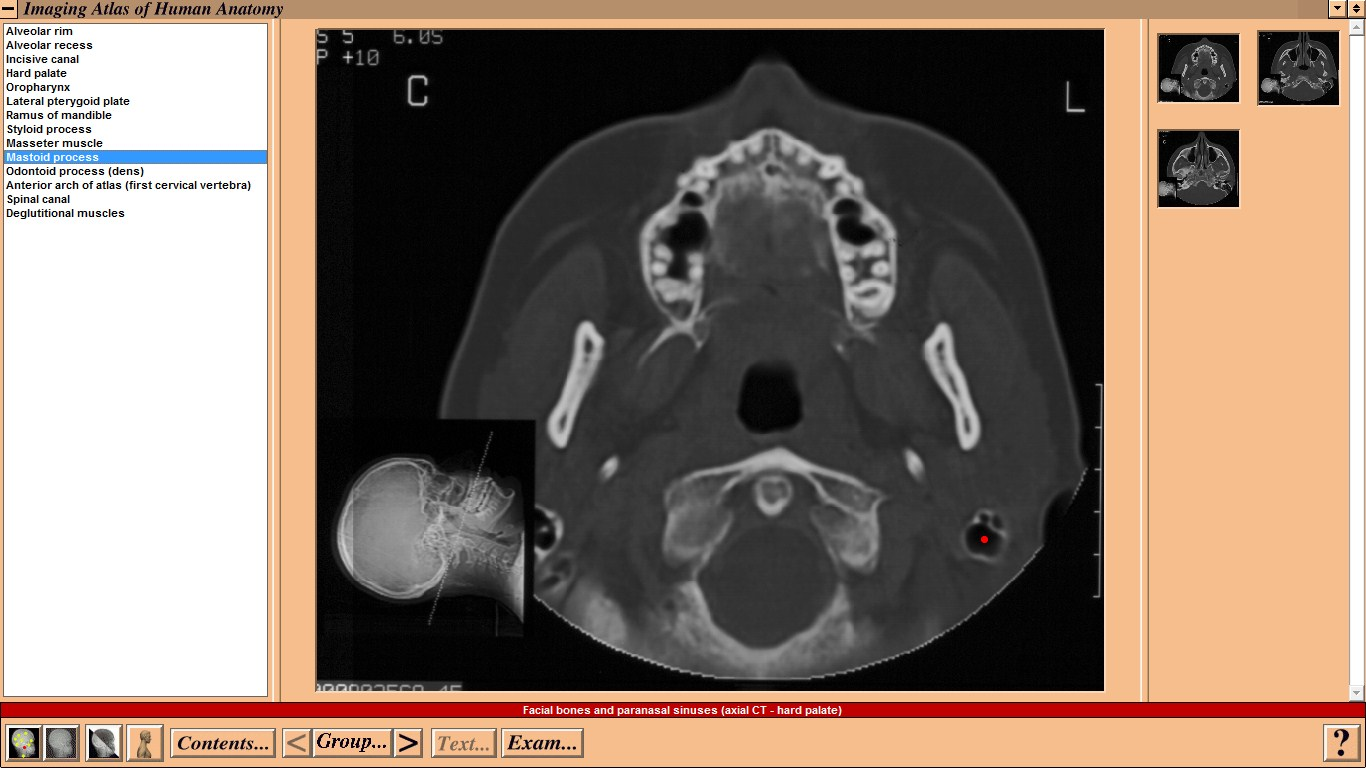

Mosby - Imaging Atlas of Human Anatomy by Jamie Weir and Peter H. Abrahams - CD-ROM

Mosby - Imaging Atlas of Human Anatomy by Jamie Weir and Peter H. Abrahams - CD-ROM Год выпуска: 1995 Версия: 1.0 Разработчик: Mosby Платформа: WindowsСовместимость с Vista: неизвестно Системные требования: IBM or compatible PC, 486SX, 8MB RAM, 640 × 480 display, 256 colors, double speed CD-ROM drive, Microsoft Windows 3.1 or later, optimum: Pentium processor, 800 × 600 display, more than 256 colors, ISBN 0-7234-2187-0, St Louis, Mo, Mosby, 1995 Язык интерфейса: только английский Таблэтка: Не требуется Описание: This CD-ROM provides a detailed atlas of radiologic anatomy in all forms, including plain films, magnetic resonance (MR) imaging, computed tomography (CT), venography, and angiography. It is formatted to present a concise atlas, cephalad (skull) to caudad (feet). The disc is easy to work with, and I did not have any trouble setting it up. The graphics and table of contents are laid out well. Navigating the various parts is relatively simple. The opening graphics are well displayed, allowing instant access to pictures or the table of contents; therein lies the simplicity of finding an anatomical part of the body to review. Each screen contains a picture of the radiograph accessed, key landmarks (with a glossary that can be turned off), related slides that can easily be accessed, and a self-exam. Диск содержит более чем 3500 радиографических изображений нормальной анатомии, включая обычные рентгенограммы, КТ, МРТ, ангиограммы, артериограммы и видео УЗИ. Исчерпывающий уровень анатомических ориентиров с возможностью самоконтроля. Издание рассчитано прежде всего на рентгенологов. Доп. информация: Поскольку издание старое, придется установить древнюю версию Quick Time - 2.0.3.51 (есть на самом диске).   Набор в группу «Хранители» - Помогите сохранить редкие раздачи Mosby - Imaging Atlas of Human Anatomy by Jamie Weir and Peter H. Abrahams - CD-ROM Год выпуска: 1995 Версия: 1.0 Разработчик: Mosby Платформа: Windows Совместимость с Vista: неизвестно Системные требования: IBM or compatible PC, 486SX, 8MB RAM, 640 × 480 display, 256 colors, double speed CD-ROM drive, Microsoft Windows 3.1 or later, optimum: Pentium processor, 800 × 600 display, more than 256 colors, ISBN 0-7234-2187-0, St Louis, Mo, Mosby, 1995 Язык интерфейса: только английский Таблэтка: Не требуется Описание: This CD-ROM provides a detailed atlas of radiologic anatomy in all forms, including plain films, magnetic resonance (MR) imaging, computed tomography (CT), venography, and angiography. It is formatted to present a concise atlas, cephalad (skull) to caudad (feet). The disc is easy to work with, and I did not have any trouble setting it up. The graphics and table of contents are laid out well. Navigating the various parts is relatively simple. The opening graphics are well displayed, allowing instant access to pictures or the table of contents; therein lies the simplicity of finding an anatomical part of the body to review. Each screen contains a picture of the radiograph accessed, key landmarks (with a glossary that can be turned off), related slides that can easily be accessed, and a self-exam. Диск содержит более чем 3500 радиографических изображений нормальной анатомии, включая обычные рентгенограммы, КТ, МРТ, ангиограммы, артериограммы и видео УЗИ. Исчерпывающий уровень анатомических ориентиров с возможностью самоконтроля. Издание рассчитано прежде всего на рентгенологов. Доп. информация: Поскольку издание старое, придется установить древнюю версию Quick Time - 2.0.3.51 (есть на самом диске).   Набор в группу «Хранители» - Помогите сохранить редкие раздачи Программы и Дизайн » Системы для бизнеса, офиса, научной и проектной работы » Медицина - интерактивный софт